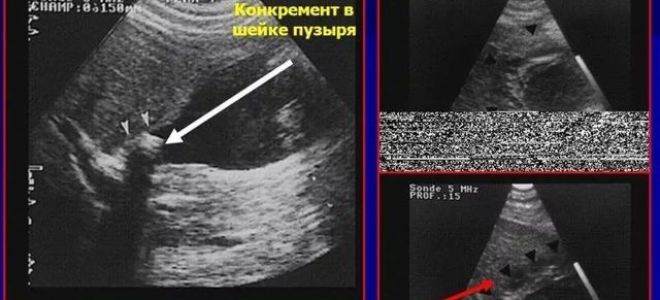

Калькулезный холецистит: причины заболевания, характерные симптомы и способы лечения

Это происходит в том случае, когда в желчном пузыре присутствуют камни.